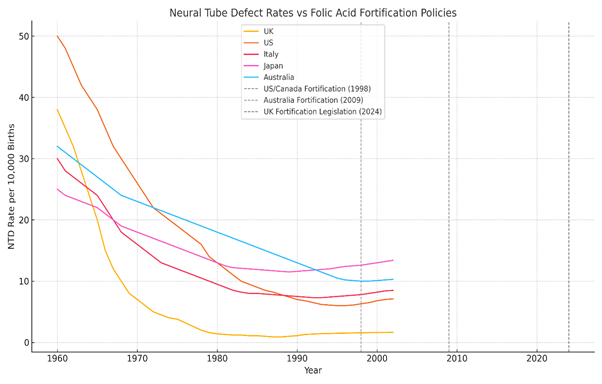

5: Neural Tube Defect (NTD) Global Birth Trends & Pharmaceutical Influence

This section of the report tracks the historical prevalence of neural tube defects (NTDs) across the UK, US, Italy, Japan, and Australia, cross-referencing these trends with key pharmaceutical events, drug regulations, and folic acid fortification policies. The objective is to identify whether the decline in NTDs is solely due to folic acid fortification, or whether external factors, such as the reduction of teratogenic drugs, played a more significant role.

Italy NTD Birth Trends:

Pre-1998 Data (Before Fortification Policies in Other Nations)

- Italy has never implemented mandatory folic acid fortification, making it a useful case study to compare against fortified nations.

- Early studies suggest NTD rates fluctuated but showed gradual declines due to improved medical practices.

Post-2000 Trends

- Italy promotes folic acid supplementation rather than fortification, encouraging women to take folic acid preconceptionally. A Central Italy anomaly study (2002–2004): → 18.5 per 10,000 births in localized area (Stazi et al., 2008)

- Despite no mandatory fortification, Italy has not seen a significantly higher rate of NTDs compared to fortified nations, raising questions about whether fortification is truly necessary for NTD prevention. Folic acid promoted via supplementation guidance, not legislation

(Calzolari et al., 2001) – EU Rare Disease Project

The absence of mandatory fortification in Italy has not resulted in a notable difference in NTD prevalence when compared to fortified countries like the US and Australia. This suggests that other factors – such as dietary folate intake, genetic predispositions, and medical advancements – may be equally or more important.

Australia NTD Birth Trends:

Pre-Fortification Era (Before 2009 – Australian Institute of Health and Welfare, 2014)

- Before mandatory folic acid fortification in wheat flour (2009), Australia’s NTD rate was 4.6 per 10,000 births.

· (Despite voluntary folic acid promotion in 2009, no major decline in NTDs was observed (D’Antoine et al., 2019).

- Following the 2009 fortification mandate, data showed a 14.4% reduction in NTDs per 10,000 conceptions (D’Antoine et al., 2019).

- However, NTD rates remain higher than expected, indicating that fortification did not eliminate the issue as projected.

While folic acid fortification in Australia coincided with a reduction in NTD rates, the decline was not as drastic as predicted. The persistence of NTD cases post-fortification raises questions about whether synthetic folic acid alone is sufficient for prevention – or if biological, environmental, and dietary factors play a larger role.

Japan NTD Birth Trends:

A review of national data in Japan (Nanishi et al., 2019) demonstrates that NTD rates remained relatively stable despite the absence of mandatory folic acid fortification. This data challenges prevailing assumptions about the universality of fortification benefits and highlights the need for region-specific evaluation of public health policies.

Before and After 2000: The Unique Case of Japan

- Japan has never adopted mandatory folic acid fortification, relying instead on natural dietary sources and targeted supplementation.

- Despite this, recent studies suggest that Japan’s total NTD prevalence is not significantly higher than fortified nations – contradicting the claim that fortification is essential.

Recent Data: 2014–2015 Study

- Japan ranked 5th out of 7 developed nations for NTD prevalence, with rates estimated at 8.38–8.74 per 10,000 deliveries.

- However, this was 1.5x higher than previous official estimates, indicating that underreporting may have masked the true prevalence.

Japan’s case is particularly important – it challenges the assumption that fortification is necessary to prevent NTDs. The relatively stable NTD rates despite zero mandatory fortification suggest that alternative strategies, such as dietary folate intake and prenatal care, may be just as effective (or more so) than mass fortification.

5.3 Global Perspective on Data: Does Fortification Truly Work?

The comparison of these nations reveals an uncomfortable reality:

- Access to raw data has been disrupted since 2011 (Modgil et al., 2022; Wozniak & Bianchi, 2019).

- NTDs declined significantly in many countries before fortification was introduced (De Wals et al., 2007; Wald et al., 2001).

- Countries without fortification (Italy, Japan) have not suffered drastically higher NTD rates and the NTD rates that they do have may well be aligned with their teratogenic drug prescribing practices (D’Angelo et al., 2017; Ueda et al., 2016).

- In fortified nations, NTDs did decline post-fortification, but not to the extent predicted, and it is important to remember that correlation does not equal causation. (Best et al., 2024; Crider et al., 2011).

Recent data suggests that some countries (including the UK and US) may be seeing a plateau and increase in NTD cases, despite ongoing fortification policies (Molley et al., 2023; Greenblatt et al., 2021).

The assumption that mandatory folic acid fortification is the sole reason for NTD reduction is now in serious question. Other factors -including elimination of teratogenic drugs, dietary improvements, genetic factors, and medical interventions – must be considered.